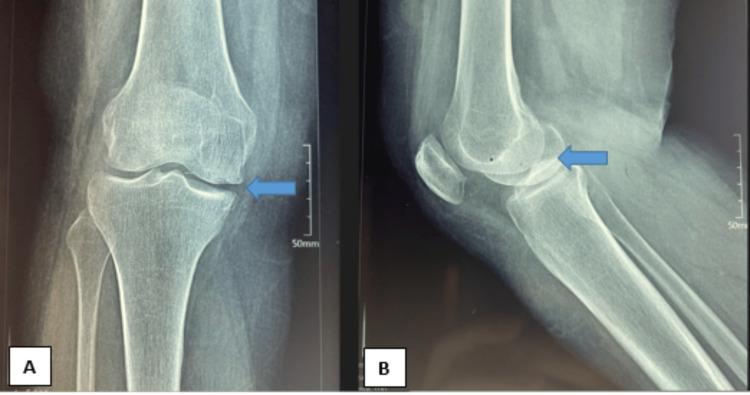

Mucoid degeneration (MD) is an uncommon pathological phenomenon that specifically affects the anterior cruciate ligament (ACL). This condition arises from the infiltration of yellowish material within the fibers of the ACL, contributing to the clinical presentation characterized by discomfort and limited mobility. MRI has proven to be the foremost diagnostic modality in effectively distinguishing MD of ACL from other potential pathologies. Preoperative recognition of this condition facilitates straightforward diagnosis, particularly via characteristic findings observed during knee arthroscopy. We present a case of MD of ACL, review prior studies about the condition, and outline its clinical features and symptoms, including those observed in our specific case.

黏液样变性(MD)是一种罕见的病理现象,专门影响前交叉韧带(ACL)。这种情况源于ACL纤维内淡黄色物质的浸润,导致以不适和活动受限为特征的临床表现。MRI已被证明是有效区分ACL的MD与其他潜在病变的首要诊断方式。术前识别这种情况有助于直接诊断,特别是通过膝关节镜检查时观察到的特征性表现。我们报告一例ACL的MD病例,回顾先前关于该疾病的研究,并概述其临床特征和症状,包括在我们这个特定病例中观察到的情况。